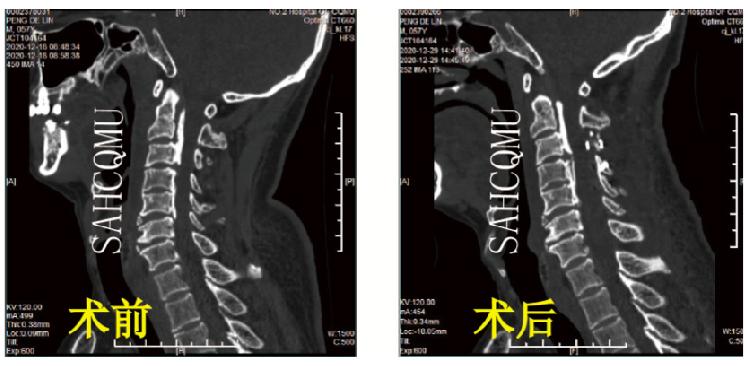

(颈椎后路单开门椎板扩大成形术·术前术后对比)

但如果遇到:颈椎病变的节段太多、太高;广泛的颈椎后纵韧带骨化症;黄韧带肥厚、骨化、椎板增生肥厚等;下颈椎骨折脱位如合并单、双侧关节突交锁等情况是,前路手术困难且减压不彻底,我们会采取后路手术。汪洋介绍,颈椎后路开门手术就是将脊髓后面的椎板和韧带从上到下,从一侧或两侧翻开,扩大脊髓后方的空间, “来自前方的压迫虽然还在,但是脊髓可以向后躲避,这样一来压迫也就解除了。”